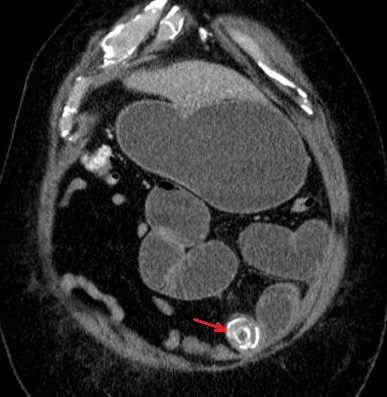

Image une calcul a

infundubulum du vesicule biliaire ( fleche

rouge ) avec epaississement de la paroi

vesiculaire : Image TDM en coupe axiale

avec contrast intraveineuse |